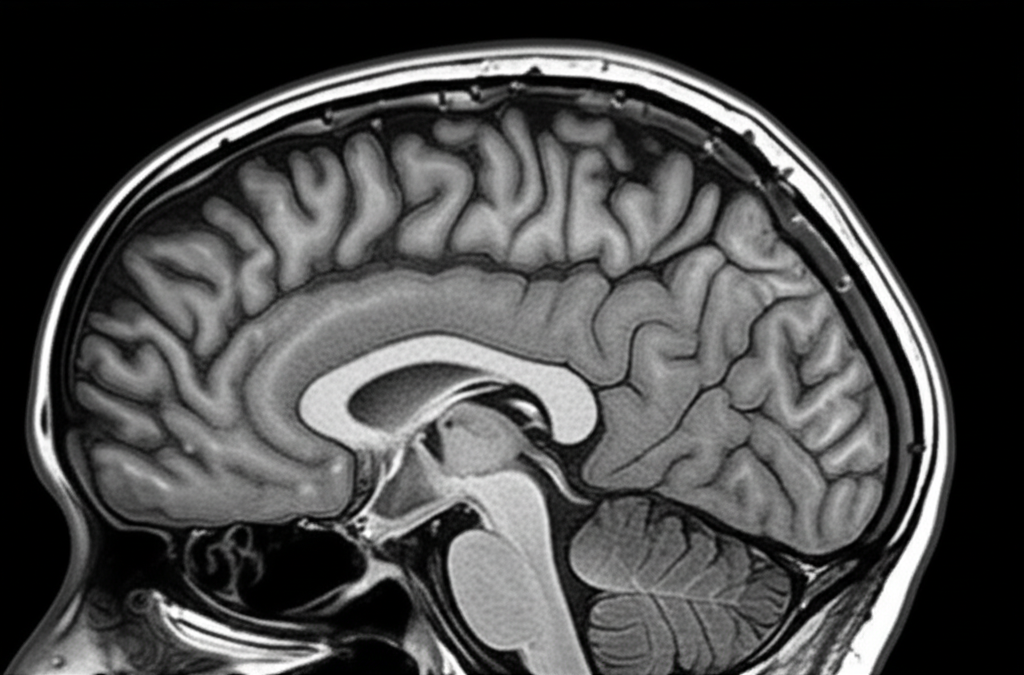

The neurologist explained that what seemed like early dementia symptoms were actually the cumulative effect of how alcohol affects the brain differently after menopause. A brain scan showed subtle changes in her hippocampus - the memory center that becomes particularly vulnerable to alcohol's effects in women over 55.